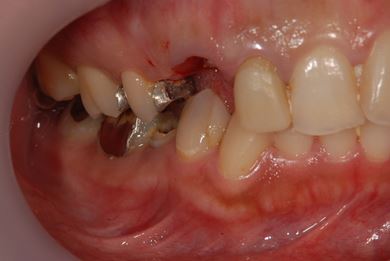

| 性別/年齢 | 女性 / 29歳 | ||||||||||||||||||||||||||||||||

| 主訴 | 以前治療中のままだった部位の歯の根に膿が溜まって、痛みと腫れが出た。応急処置で切開して膿は取ってもらったが、根の治療がまだなので、お願いしたい。 | ||||||||||||||||||||||||||||||||

| 治療方針 | 抜歯と同時にインプラント埋入を行い、治療期間を短縮する。 | ||||||||||||||||||||||||||||||||

| 治療内容 | インプラント2本(抜歯即日スピードインプラント)、ハイブリッドセラミッククラウン3本 | ||||||||||||||||||||||||||||||||